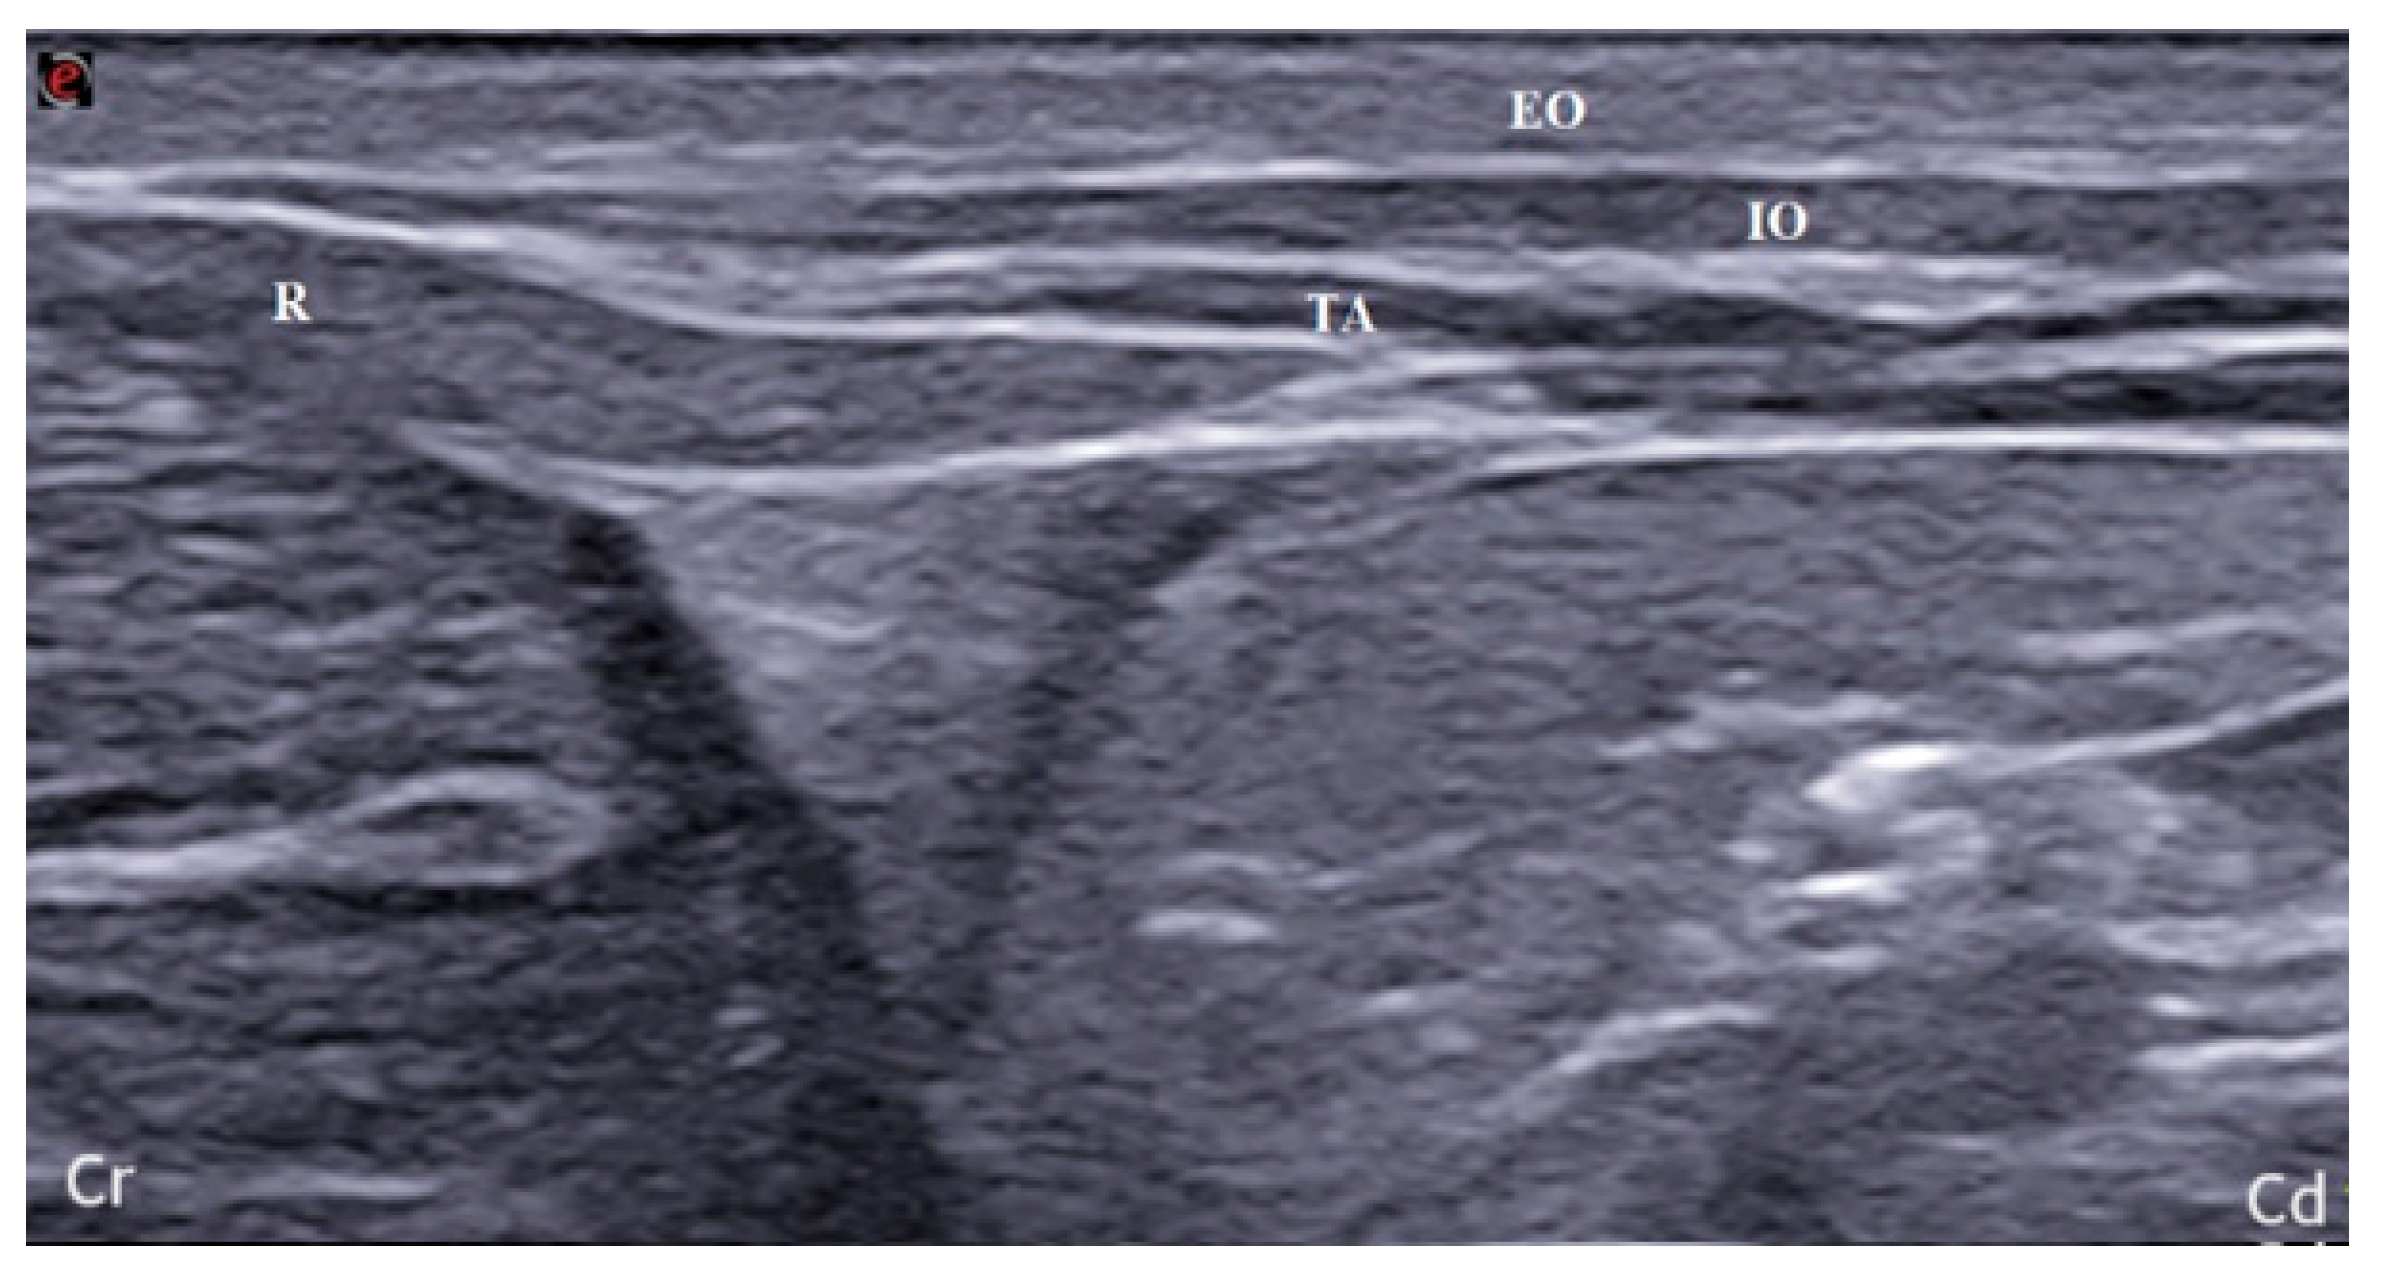

2.1. US-Guided TAP Injection

3.1. US-Guided TAP Injection

3.2. Anatomical Dissection and Measurement